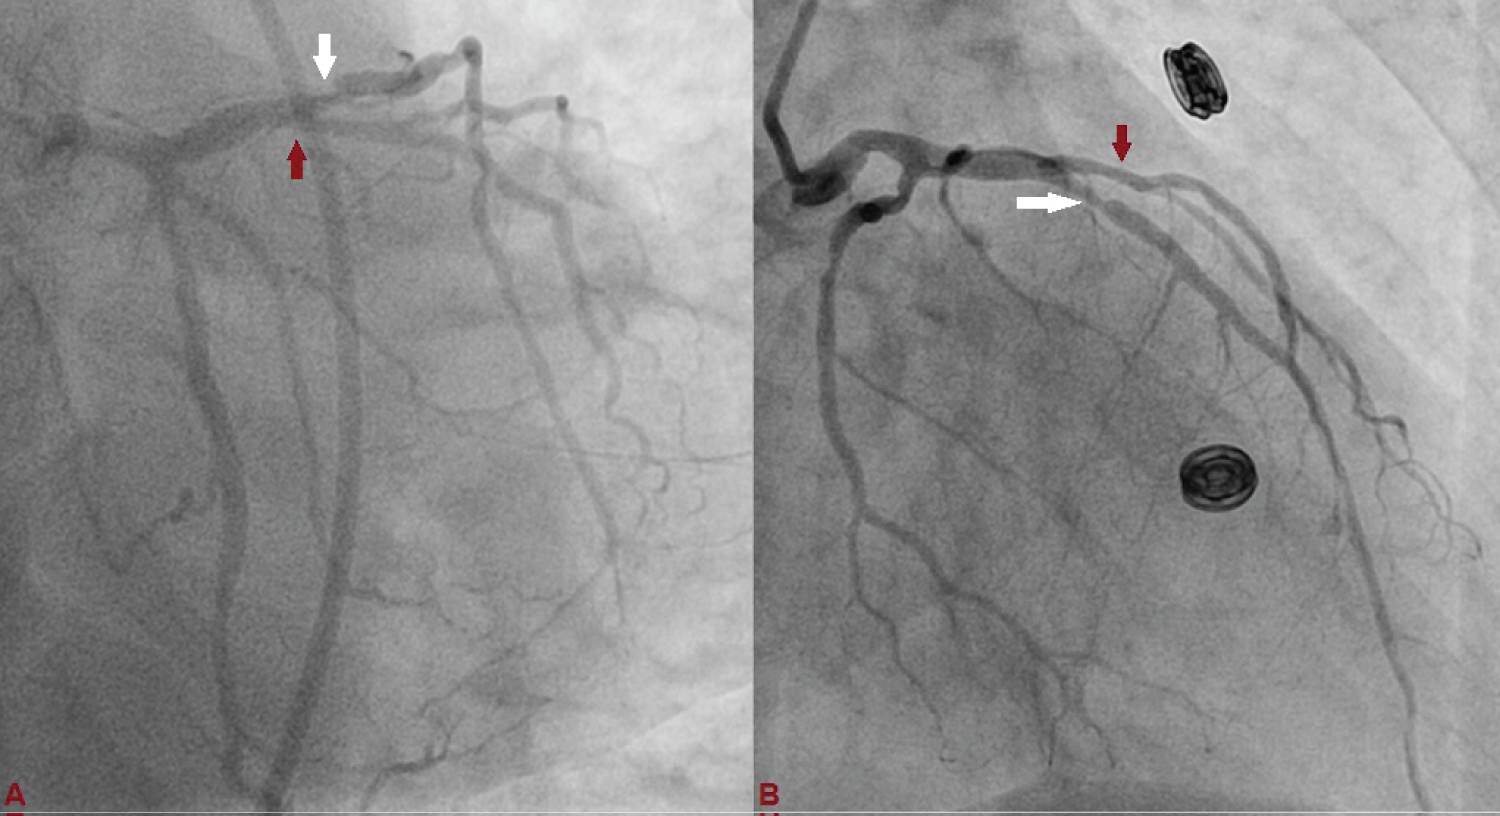

A 75-year-old diabetic and hypertensive male presented with chest heaviness with sweating of 6 hours duration. An electrocardiogram showed marked ST elevation in V1-V6. Routine haemogram and biochemistry was normal except deranged renal function with serum creatinine of 3.3 mg%. His body weight was 68 kg. Echocardiography revealed mild concentric left ventricular hypertrophy, regional wall motion defect in left anterior descending territory (LAD), and impaired systolic function with an ejection fraction of 40%. His coronary angiogram was done through transfemoral approach after proper consent revealing critical lesion with 90% stenosis in mid left anterior descending (LAD) artery just after large diagonal branch, normal left circumflex territory, and right coronary artery (Figure 1 and Figure 2). The coronary angiogram was completed using 9 ml of contrast. The contrast used was iodixanol which is an iso-osmolar contrast agent. Primary PCI was planned subsequently. Intravenous heparin (100 U/Kg) was administered. Based on all the baseline factors, it was a high risk PCI carrying a profound risk of CIN. To minimize the risk of CIN, intravenous normal saline infusion was started. Prior to PCI, initial angiogram with same angle of projection was uploaded to the monitor for PCI guidance. Left main artery was engaged with 6F extra backup guiding catheter (EBU; Medtronic, USA) which was confirmed by entry of the runthrough wire (Terumo, Japan) into the coronary artery. An exaggerated curve was created to facilitate the wiring of LAD. Additional runthrough wire was placed in first diagonal branch (D1) based on the previous angiogram (Figure 3). The side branch wire served as an important landmark to guide PCI and to protect the side branches as well. The balloon was positioned just after D1 which was used as a landmark for proximal end for stent placement. Lesion was gradually predilated with 2 × 10 and 2.5 × 10 pantera leo semi compliant balloons (Biotronik, Germany). 3 × 23 mm Endeavour Resolute (Zotarolimus eluting stent; Medtronic, USA) stent was positioned across the lesion keeping the proximal end at the crossing of LAD and D1 wire which was serving as the origin of D1 (Figure 3). It was deployed at 13 atm pressure (Figure 4). As it was not fully expanded, it was serially post dilated by 3 × 10 and 3.5 × 10 non-compliant Minitrak balloon (Abott, USA) at 24 atm pressure. The stent apposition was checked under stent boost. After confirmation of stent optimization with stent boost, final angiography with 4 ml contrast injection revealed successful results (Figure 5). Therefore, PCI was completed using 13 ml of contrast. He was clinically stable for 2 days without CIN (Serum creatinine 3.5 mg/dL). She was discharged 2 days after PCI with appropriate drugs and has been uneventful.

Figure 1: Left anterior descending (LAD) artery revealing critical lesion with 90% stenosis in mid just after large diagonal branch (D1), and normal left circumflex artery. (A: Antero-posterior view with caudal angulation; B: Antero-posterior view with cranial angulation). View Figure 1

Figure 3: A) Basal angiographic view of left system used as anatomical reference to mark position of LAD and D1; B) 3 × 23 mm Endeavour Resolute stent was positioned across the lesion keeping the proximal end at the crossing of LAD and D1 wires which was serving as the origin of D1. View Figure 3